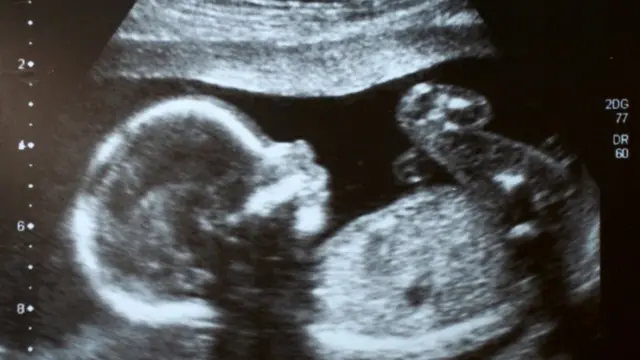

غربالگری جنینهای دارای نقص ژنتیکی در ایران با فتوای مراجع تقلید و در راس آنان آیتالله علی خامنهای تصویب و اجرا شد. حالا سیاستهای جمعیتی کلان، ایران را به سویی میبرد که در آن، شماری از محافظهکاران قصد دارند این روش علمی را محدود و حتی اثرات مفید آن را انکار کنند.

غربالگری روشی برای جلوگیری از تولد نوزادانی است که نقص کروموزومی یا ناهنجاری شدید جسمی دارند.

این روش ۱۵ سال در ایران مانع به دنیا آمدن کودکانی شده که یا زندگی مادر را به خطر میاندازند، یا عمرشان کوتاه و پرمشقت است، یا نقص کروموزومی دارند. اما ناگهان شماری از نمایندگان مجلس تصمیم گرفتهاند قوانین موجود را تغییر دهند.